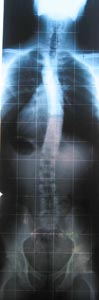

Warum habe ich bei 20 Grad so einen Rippenbuckel ?

Ich habe hier 2 Fotos reingestellt

Einmal von links und einmal von rechts ich denke der Unterschied ist deutlich zu sehen.

- 1n.jpg (28.25 KiB) 9418 mal betrachtet

Auf dem Foto sieht alles nicht so schlimm aus aber es ist die Beste Haltung die ich aus eigener Muskelkraft schaffe.

Hey Dietmar! Dein Röntgenbild sieht ja fast genauso aus wie meins!! Also, ein bissele freu ich mich darüber, hab jetzt einen konkreten Leidensgenossen.

Hab gerade nochmal mein Bild neben deines gelegt. Die Verlaufsrichtungen sind zwar ziemlich gleich, aber der Krümmungswinkel ist bei dir auf jeden Fall etwas größer. Ich würde also schätzen, dass du thorakal auf jeden Fall über zwanzig Grad bist. Leider taugen meine Bilder nichts, sonst würde ich sie dir zum Vergleich schicken. Sorry.